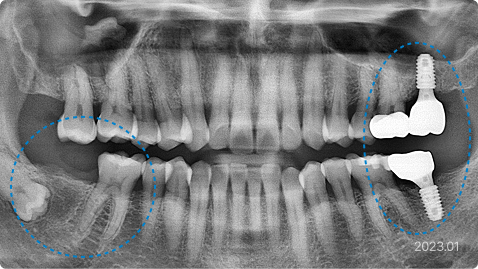

치료 내용

• 직장 사정으로 긴 치료기간과 잦은 내원이 불가하여 방치된 치아

• 의식하진정법(수면마취)으로 네 군데의 임플란트 수술, 전체 앞니 심미 보철 시행

• 힘든 진료를 모아서 시행하였고, 임플란트도 3개월만에 최종 완성